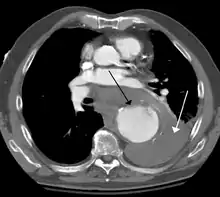

A thoracic aortic aneurysm is an aortic aneurysm that presents primarily in the thorax.

A thoracic aortic aneurysm is the "ballooning" of the upper aspect of the aorta, above the diaphragm. Untreated or unrecognized they can be fatal due to dissection or "popping" of the aneurysm leading to nearly instant death. Thoracic aneurysms are less common than an abdominal aortic aneurysm.[2] However, a syphilitic aneurysm is more likely to be a thoracic aortic aneurysm than an abdominal aortic aneurysm. This condition is commonly treated via a specialized multidisciplinary approach with both vascular surgeons and cardiac surgeons.

Diagnosis

Thoracic aortic aneurysm is defined as a cross-sectional diameter exceeding the following cutoff: